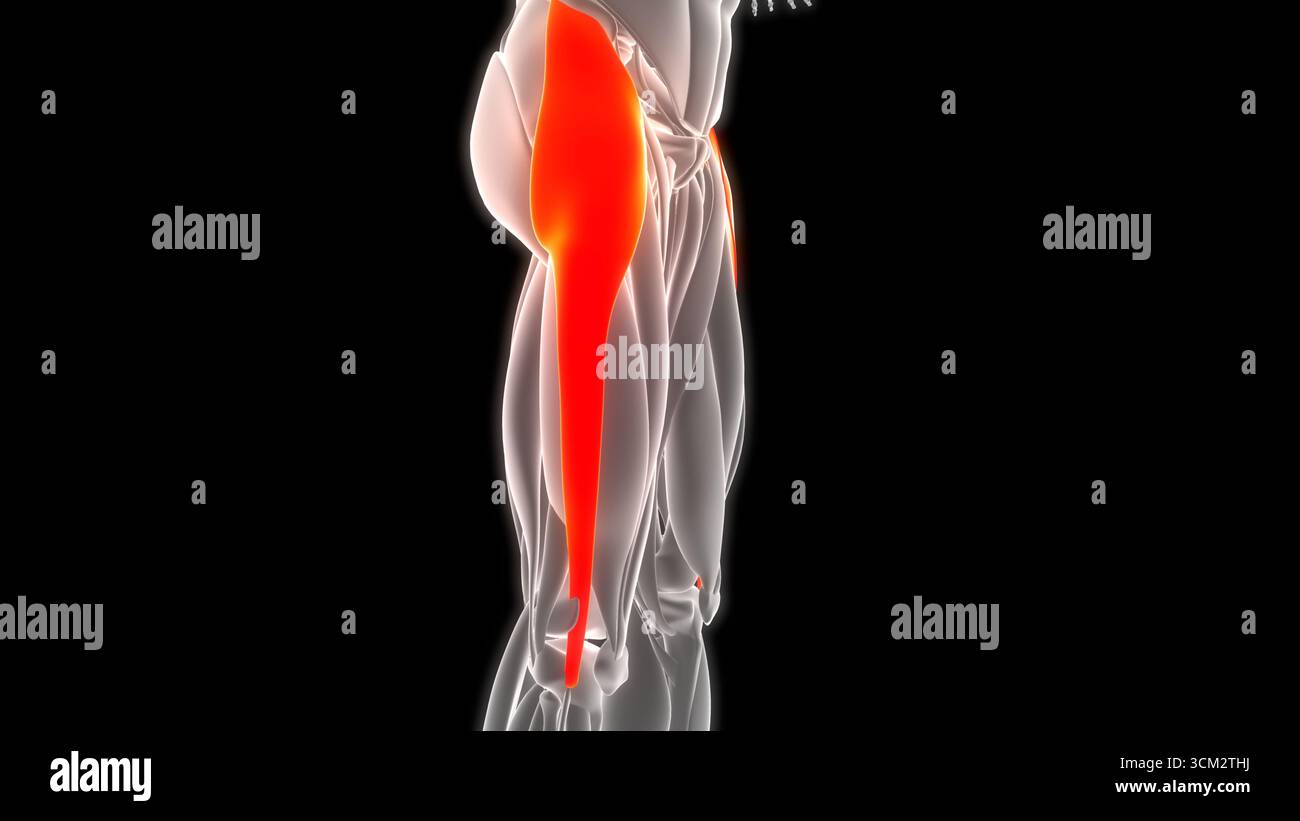

Human Muscular System Leg Muscles Tensor Fasciae Latae Muscles Anatomy Stock Photohttps://www.alamy.com/image-license-details/?v=1https://www.alamy.com/human-muscular-system-leg-muscles-tensor-fasciae-latae-muscles-anatomy-image700771054.html

Human Muscular System Leg Muscles Tensor Fasciae Latae Muscles Anatomy Stock Photohttps://www.alamy.com/image-license-details/?v=1https://www.alamy.com/human-muscular-system-leg-muscles-tensor-fasciae-latae-muscles-anatomy-image700771054.htmlRF3CM2THJ–Human Muscular System Leg Muscles Tensor Fasciae Latae Muscles Anatomy